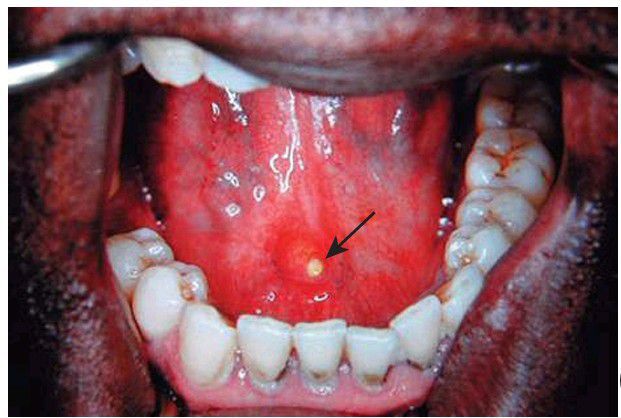

Stone in wharton duct

Stone at the orifice of the Wharton duct that is amenable to intraoral removal (arrow).